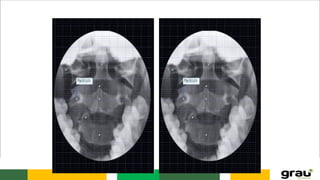

C1 (Atlas)

Ausência de corpo

C. CERVICAL

C2 (Áxis)

Processo odontóide